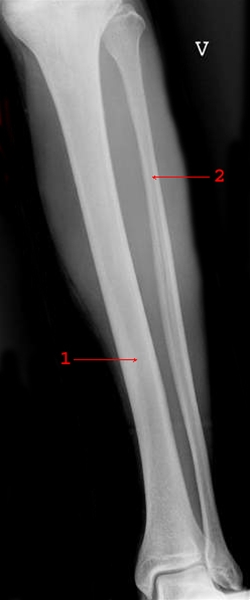

Underben, forfra

Normalt røntgenbillede med forfrabillede af tibia (1) og fibula (2)